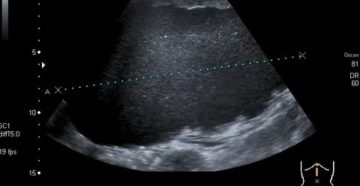

Киста яичника на УЗИ: видна ли, как определить вид образования В яичниках (женских гонадах) с…